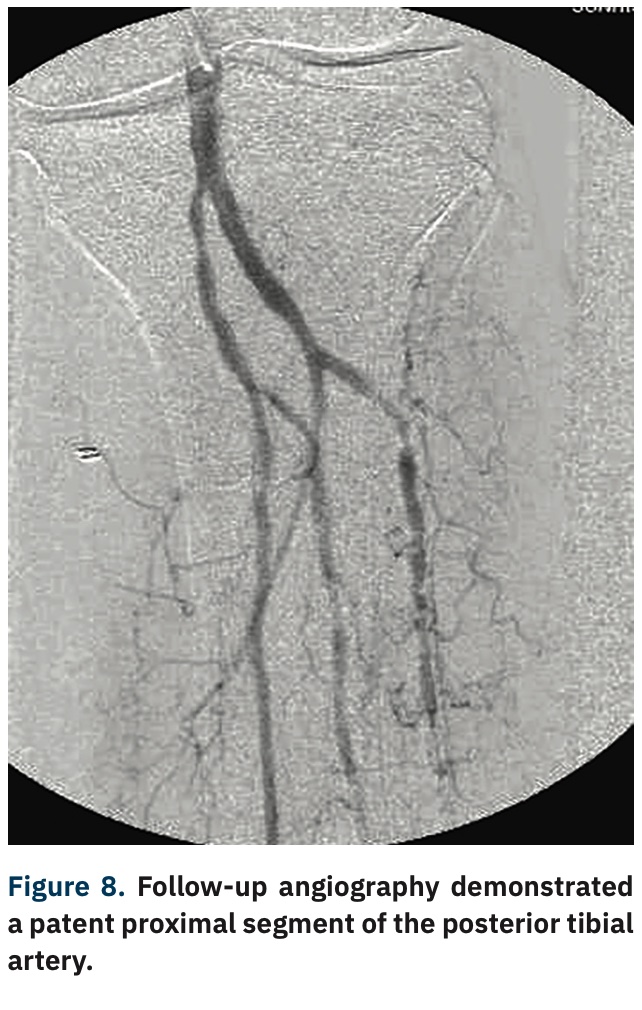

TCTAP C180 Reverse CART Technique in Above Knee Peripheral CTO Cart And Reverse Cart Technique Stent reverse cart entails creation of an open target for retrograde guidewire navigation when a stent is. The “stent reverse cart” technique involves deploying a stent within the antegrade dissected plane to create an open target for retrograde crossing. Controlled antegrade and retrograde subintimal tracking (cart) and reverse cart. Two rdr techniques are available: The most commonly used retrograde crossing. Cart And Reverse Cart Technique.